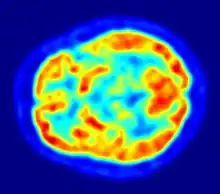

PET scan of the human brain

PET imaging with oxygen-15 indirectly measures blood flow to the brain. In this method, increased radioactivity signal indicates increased blood flow which is assumed to correlate with increased brain activity. Because of its 2-minute half-life, oxygen-15 must be piped directly from a medical cyclotron for such uses, which is difficult.[17]

PET imaging with FDG takes advantage of the fact that the brain is normally a rapid user of glucose. Standard FDG PET of the brain measures regional glucose use and can be used in neuropathological diagnosis.